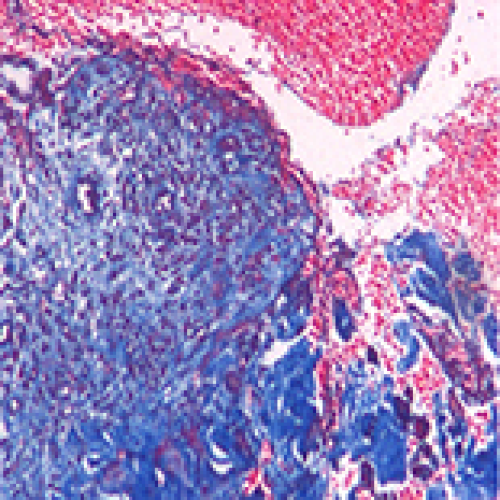

Impact of Hyperbaric Oxygen on Tissue Healing around Dental Implants in Beagles

Juan Liao, Meng-Jun Wu, Yan-Dong Mu, Peng Li, Jun Go

DOI: 10.12659/MSM.912784

Med Sci Monit 2018; 24: ANS8150-8159